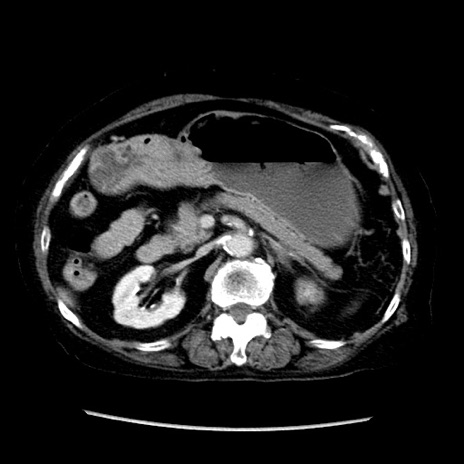

症例14(横断像)

【症例】 90歳代女性

【主訴】 腹痛・嘔吐

【現病歴】今朝から左側腹部痛を認めた。 経過観察していたが、嘔吐を認めたため来院。

【既往歴】 子宮癌術後

【身体所見】 意識清明、BP 127/54mmHg、P 98bpm Sp02 95%(RA)、BT 35.8°C、腹部平坦・軟腸ぜん動音聴取良好、右下腹部圧痛(+) 反跳痛なし

【データ】WBC 9800、CRP 0.46